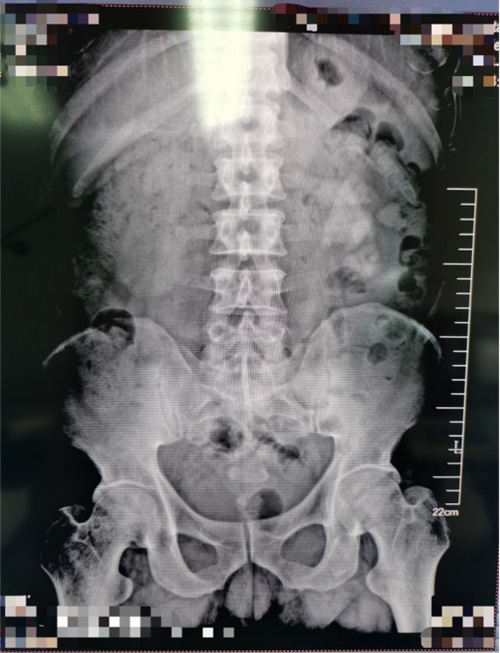

患者,男,46岁,主因左侧腰腹部间断性疼痛10天。于我院查泌尿系CT示左肾鹿角状结石、右肾结石收入院。后在可控负压吸引下行输尿管软镜钬激光碎石术治疗肾结石。

术前视图如下: